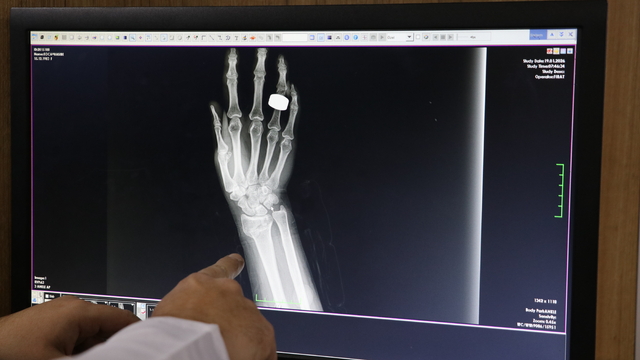

MEHMET SIDDIK KAYA / SUAT ÖZTÜRK / EKREM PAYAN - Diyarbakır, Elazığ ve Şırnak'ta son günlerde etkili olan kar ve buzlanma, düşmeye bağlı kırık vakalarında artışa neden oldu.

Üç ilde etkili olan soğuk ve karlı havanın ardından yol ve kaldırımlarda oluşan buzlanma sebebiyle çok sayıda kişi düşme sonucu meydana gelen kırıklar nedeniyle hastanelere başvurdu.

Karla birlikte buzlanmaya bağlı düşmeler yaşandığını, bu nedenle acil servislere başvuran hasta sayısında artış görüldüğünü bildiren Şen, üniversite hastanesine kar ve buzlanmada düşmeye bağlı yaklaşık 300 hasta girişinin olduğunu belirtti.

Şen, "İlimiz merkezinde hizmet veren 3 büyük hastanedeki verilerle toplam 1500 civarında hastanın bu sebeple hastanelere başvurduğunu düşünmekteyiz." dedi.

Kar yağışı ve ardından oluşan buzlanmanın düşme vakalarını artırdığını vurgulayan Gül, "Genellikle buzlu zeminde kayma ve araçların kayması sonucu meydana gelen trafik kazaları nedeniyle başvurular oluyor. Bu düşmeler sonucunda el ve ayak bileği kırıkları başta olmak üzere leğen kemiği, kuyruk sokumu ve omurga kırıkları da görülebiliyor." dedi.